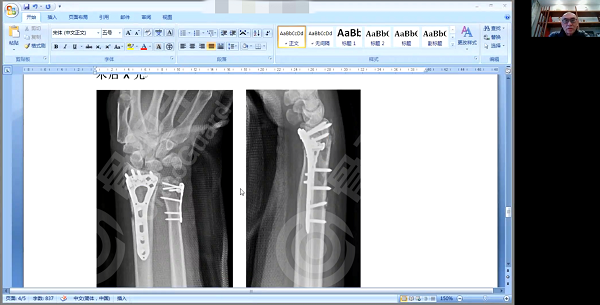

病例一

病例一是一位47岁女性患者,因摔倒导致右侧尺、桡骨远端粉碎性骨折,手法复位后第六天X光发现骨折断端有移位,外固定没有达到很好地稳定作用,经过讨论给予患者切开内钢板螺丝钉固定复位治疗。

杨述华教授表示,该患者是粉碎性骨折、闭合性骨折,X线+CT足以诊断骨折类型。在治疗方面,杨述华教授介绍了三种治疗方法:一是闭合复位。闭合复位属于中西医治疗骨折的一种方式,复位后可采用小夹板或石膏进行固定。闭合复位适用于没有移位及神经、血管损伤的四肢骨折;二是开放手术复位。开放手术可以使骨折断端完整复位,达到解剖标准,这当前采取较多的复位方式;三是介于闭合复位和开放复位之间的方式,采用外固定器固定,以微创的形式进行,只需要很小的切口即可复位骨折断端。杨述华教授特别指出,要特别关注该患者的康复锻炼,早期进行腕关节和肘关节锻炼,能在骨折愈合的同时,腕关节和肘关节也能恢复正常功能。